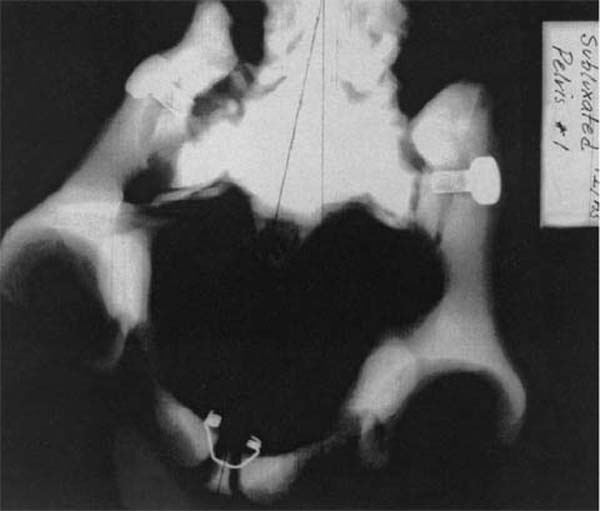

However, when the sacrum is rotated, its position in relationship to the innominates is altered and the normal perimetry of the pelvic bowl is distorted. Due to the unique diarthrotic and amphiarthrotic nature of the sacroiliac joint, as the sacrum rotates the adjacent ilium moves along one axis of motion either posteroinferiorly or anterosuperiorly. [73–75] This movement is denoted by the change in the position of the posterosuperior iliac spine (PSIS).

Figure 2 is an S to I radiographic view of a model demonstrating pelvic perimetry when the ilia have rotated posteroinferiorly and anterosuperiorly, as described above.

Note the lack of symmetry and distortion of the roundness of the pelvic bowl. Observe also the differences in space from the centerline through the pubic symphysis to each lateral aspect of the pelvic bowl. Figure 3 is an S to I radiographic view of a model demonstrating pelvic perimetry when the ilia have rotated externally and internally, as previously described.

| Figure 2.

PI/anterosuperiorly subluxated female pelvic bowl.

(Model) S to I view. Note lack of

symmetry and distortion of

roundness of opening.

Also note difference in

space from centerline

through pubic symphysis.

(Radiograph provided courtesy

of Cherie Goble, DC.)